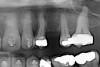

Figure 4b  Progress photo and panorex 9 months after corticotomies were performed on Nos. 6 through 11 (B and C). Previous extraction sites were reopened orthodontically to improve function and fill lip support. Incisal edges were restored provisionally with composite resin. Note that despite the creation of adequate spaces to replace missing teeth, there is inadequate room for placement of dental implants because of severe tipping of all the anterior teeth. Osteotomy SFOT may have been a better choice because it would have allowed needed alveoloskeletal correction (without excessive tipping) instead of the primarily dentoalveolar correction common in corticotomy SFOT. Restorative dentist: Brad Jones, DDS.

Figure 4b

Figure 4c  Progress photo and panorex 9 months after corticotomies were performed on Nos. 6 through 11 (B and C). Previous extraction sites were reopened orthodontically to improve function and fill lip support. Incisal edges were restored provisionally with composite resin. Note that despite the creation of adequate spaces to replace missing teeth, there is inadequate room for placement of dental implants because of severe tipping of all the anterior teeth. Osteotomy SFOT may have been a better choice because it would have allowed needed alveoloskeletal correction (without excessive tipping) instead of the primarily dentoalveolar correction common in corticotomy SFOT. Restorative dentist: Brad Jones, DDS.

Figure 4c